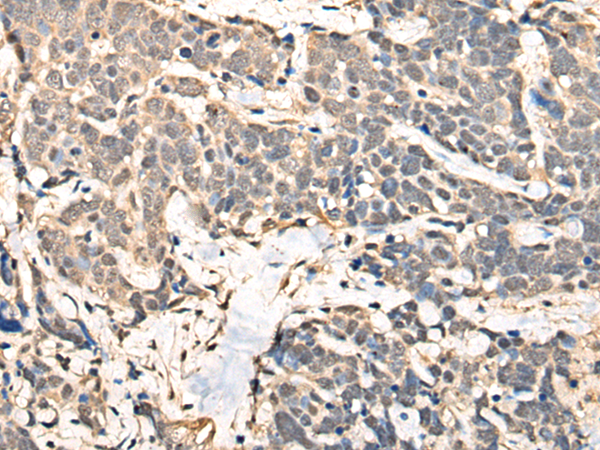

IHC positive control: |

Human ovarian cancer and human thyroid cancer |